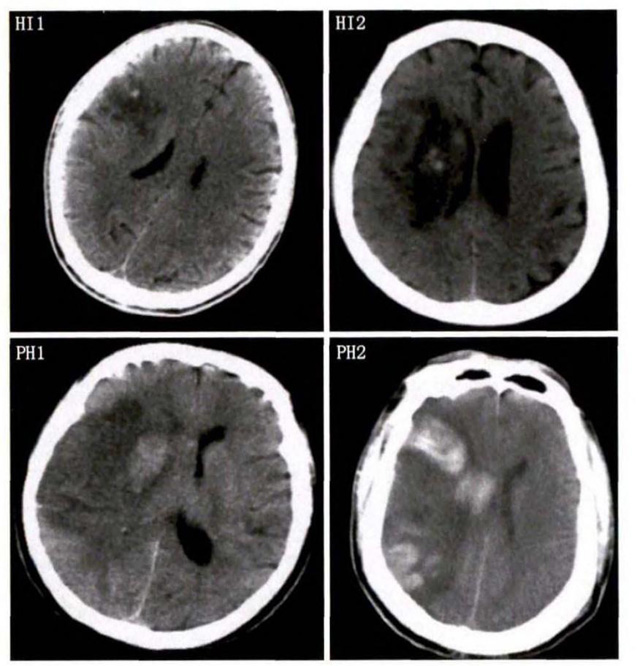

中、老年病患,有动脉粥样硬化及高血压病等脑卒中的危险因素,发病结合神经系统症状和体征,应当考虑急性脑梗死的可能。再经脑CT/MRI发现梗死灶,或排除脑出血、炎症性疾病等,诊断即可确定。脑梗死有时颇似小量脑出血的临床表现。脑栓塞在任何年龄都可以有发病的风险,可以在几秒到几分钟达到顶峰。会有偏瘫不能说话等局部神经功能损坏。栓子来源很种,可能是冠心病、心肌梗塞、心内膜炎等。合并心房纤颤,结合其他脏器官的支持诊断,CT跟磁共振都可以检查确定栓塞位置数量还有是不是有伴发出血等问题。可以帮助诊断。

中老年有高血压糖尿病发病病史,起病神经功能缺损症状,临床表现为腔隙综合征,即可初步诊断本病。如果CT或磁共振证实有与神经功能缺失一致的脑部腔隙病灶, 符合大脑半球或脑干深部的小穿通动脉病变,即可明确诊断。少数患者隐匿起病,无明显临床症状,在影像学检查时发现。